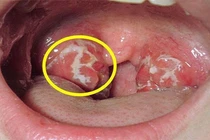

Người đàn ông ở TP HCM phải cắt bỏ lưỡi vì một vết loét nhỏ. Nhiều người nhầm ung thư lưỡi với nhiệt miệng, đến khi đau kéo dài gây khó nói, nhai, chảy máu lưỡi,…mới đi khám thì bệnh ở giai đoạn muộn, di căn đến phổi, gan..,

(khoahocdoisong.vn) - Ung thư vòm họng là bệnh lý khá phổ biến, tốc độ phát triển tương đối nhanh. Hiện nay, điều trị trúng đích ở giai đoạn sớm, bệnh nhân có thể khỏi bệnh.